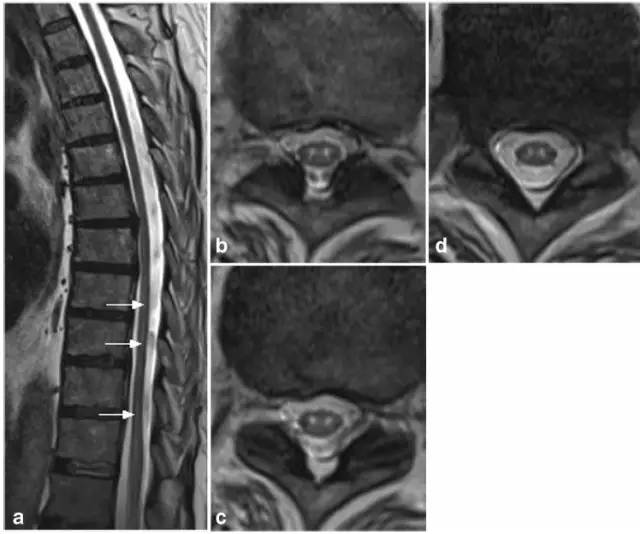

病例7:71岁男性,腹部外科手术后在ICU发生顽固低血压,导致脊髓前动脉分布区血流动力学性梗死。矢状位T2显示铅笔画样高信号(图a,箭头),轴位T2(图b-d)显示蛇眼征